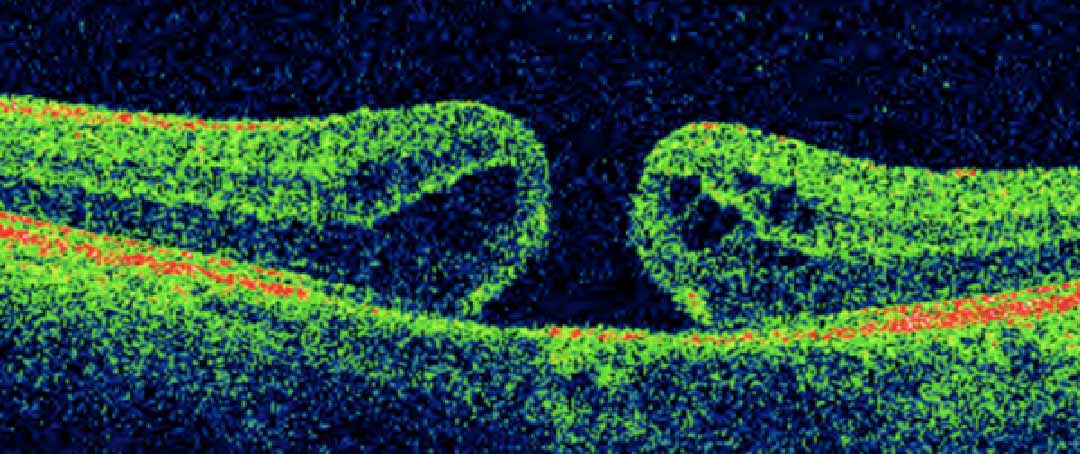

Macular hole is a disease that is caused by a hole at the centre of the eye.

Refer below picture to understand more :

One possible risk factor is a condition called vitreomacular traction. As you get older, the vitreous jelly in the middle of your eye starts to pull away from the retina and macula at the back of the eye. If some of the vitreous jelly remains attached, it can lead to a macular hole.

First, the vitreous jelly is removed (vitrectomy) and then a very delicate layer (the inner limiting membrane) is carefully peeled off the surface of the retina around the hole to release the forces that keep the hole open.